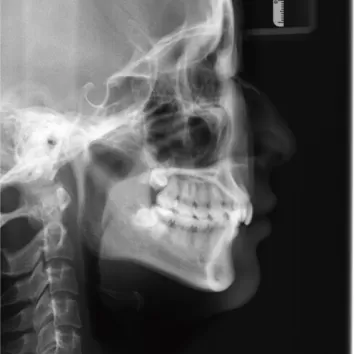

Rayons X avant le traitement

[Radiographie panoramique/Céphalogramme latéral]